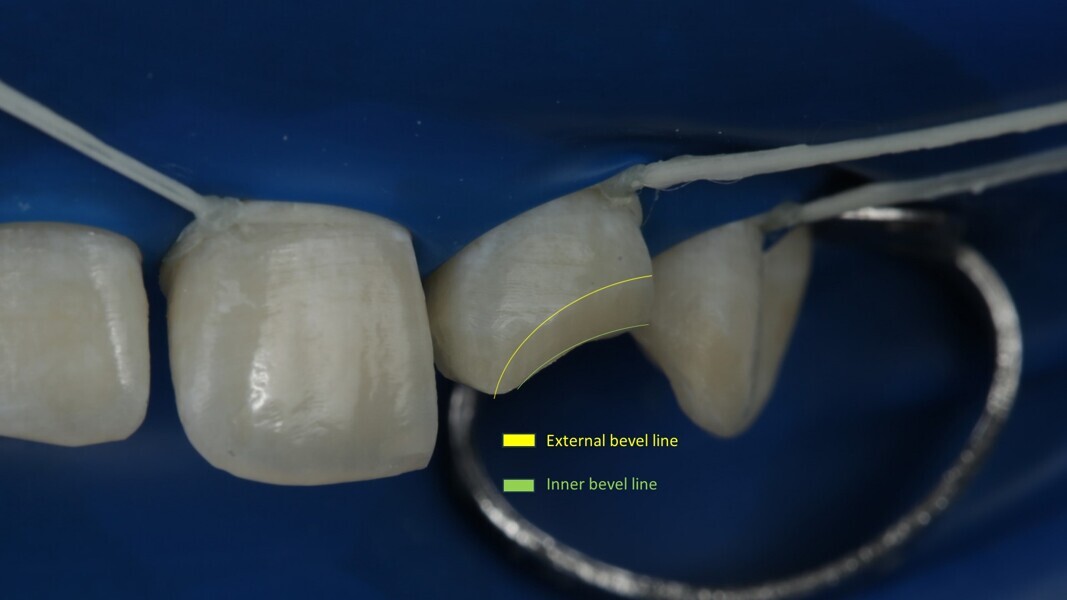

Fig 25-30: Layering protocol step by step